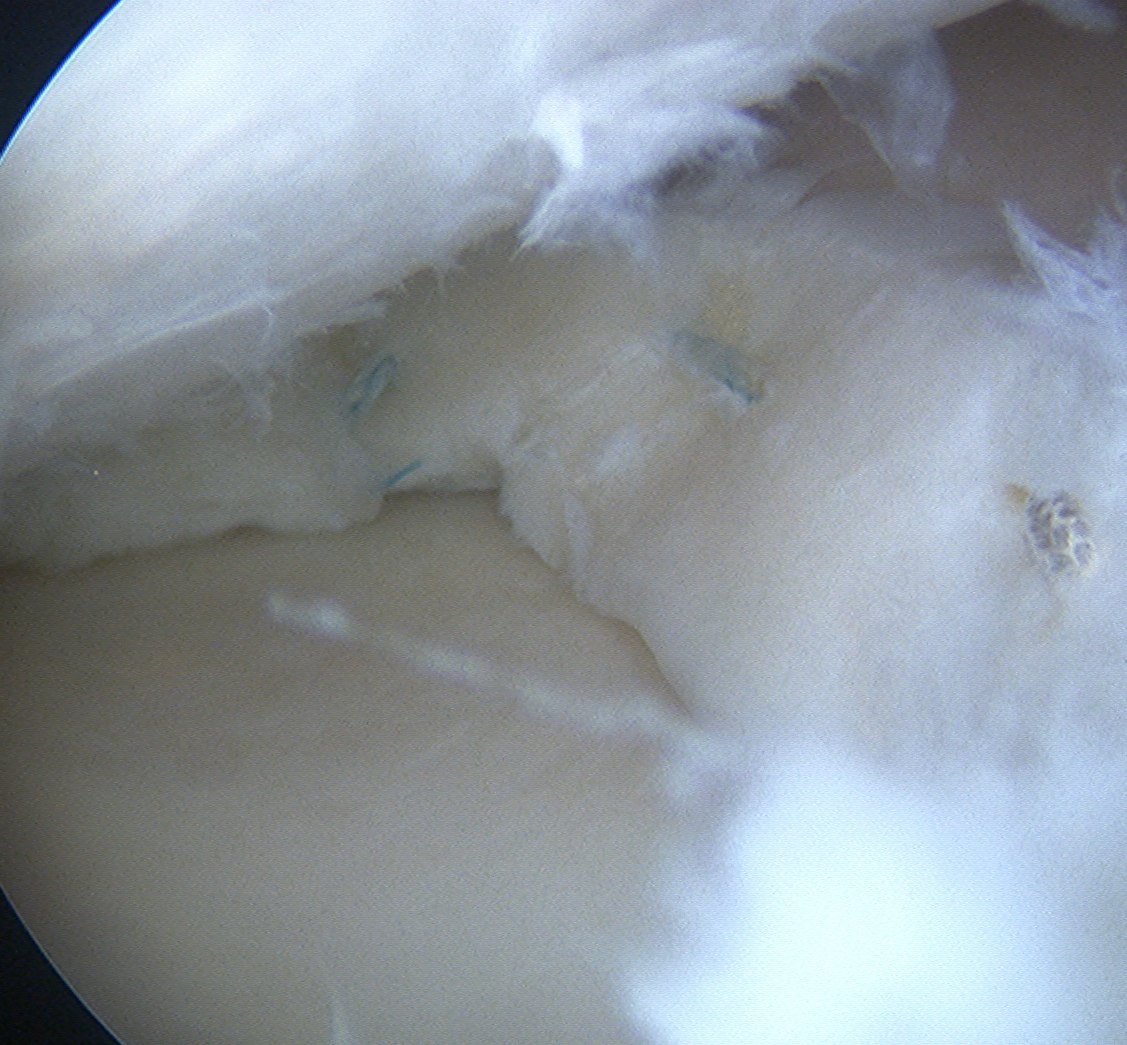

3. All inside

Instruments

- meniscal arrows (Biostinger, Meniscus Arrow)

- meniscal screws

- meniscal suture anchors (FasT-Fix, RapidLoc)

Technique FasT - Fix

- ipsilateral portal to view

- contralateral portal for instruments

- 2 x absorbable sutures anchors posteriorly

- may have to change portals for mensical body sutures

- pass first bioabsorbable anchors through meniscus and capsule

- retract and advance second anchor

- place anchor through meniscus (horizontal) or into capsule alone (vertical)

- advance knot, cut